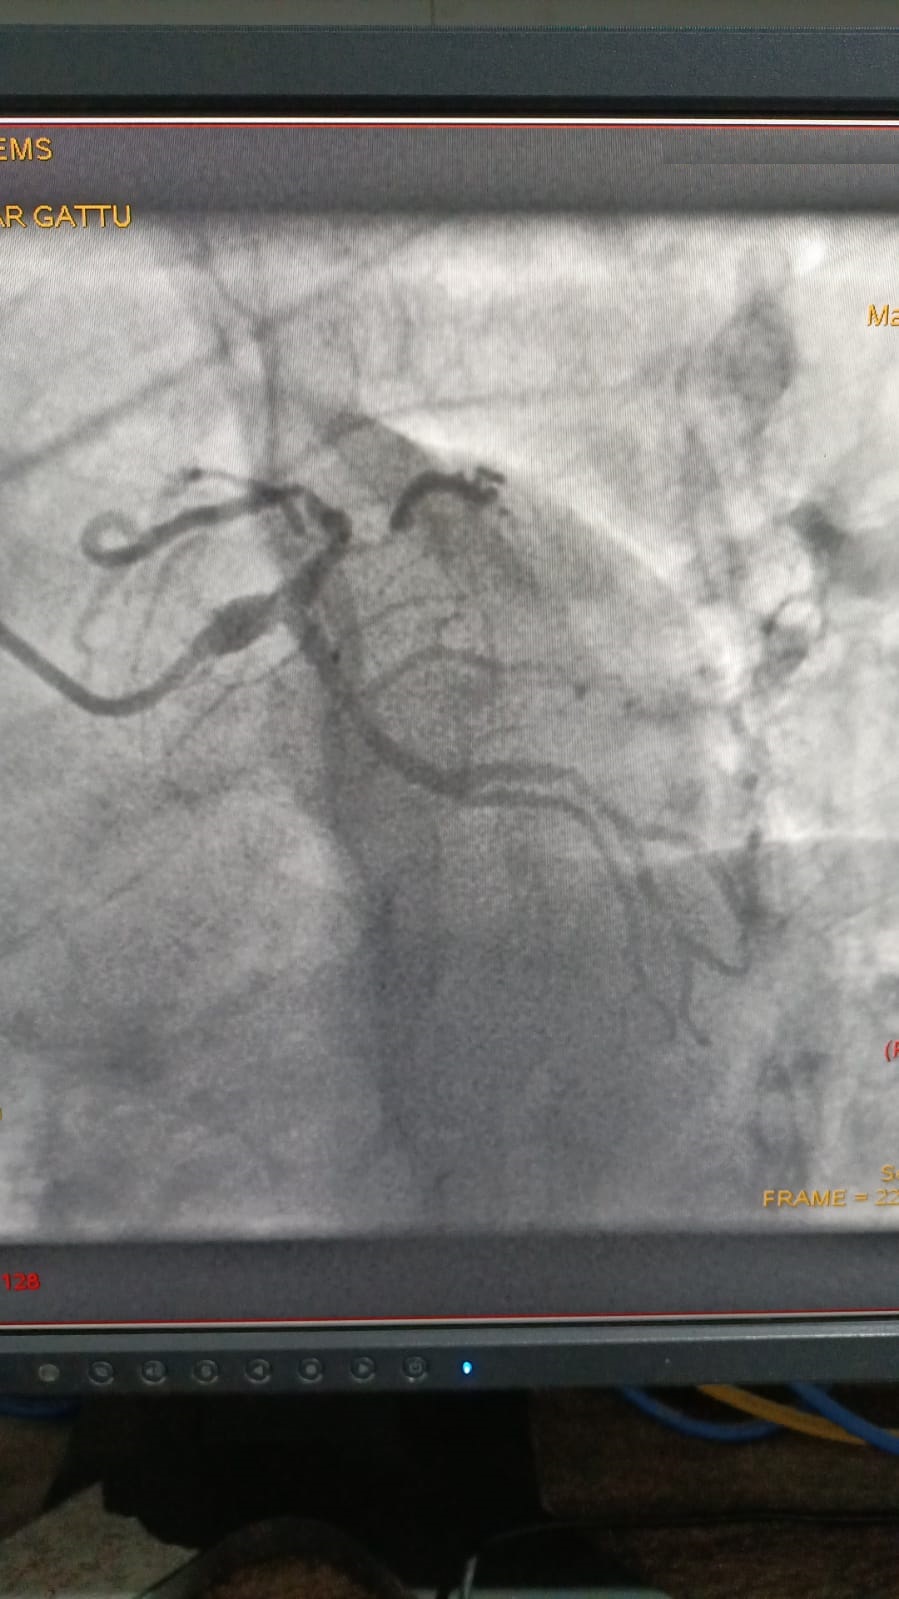

Left Coronary Diseased Artery

Right Coronary Diseased Artery